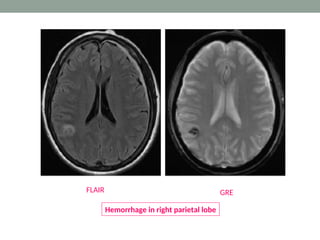

Gradient echo (GRE)

• This feature of GRE sequences is exploited- in detection

• The main clinical application of GRE sequence is

detection of hemorrhage, micro bleeds, iron deposition

GRE

FLAIR

Hemorrhage in right parietal lobe